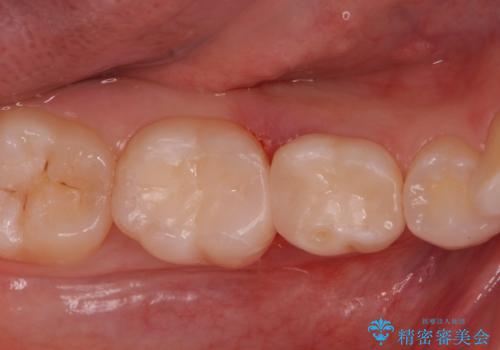

歯が染みる。セラミックインレー治療。

レントゲンを撮影したところ虫歯がありましたので拡大鏡下で虫歯を取り除いた後、e-maxインレーにて治療を行いました。

手前の歯は乳歯でしたが、患者様と相談しなるべく長持ちさせたいとの事でしたのでe-maxインレーでの治療となりました。

適合の良い詰め物が入りました。